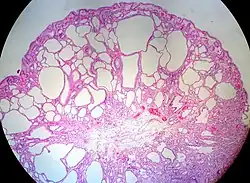

| On histopathology, a fundic gland polyp displays cystically dilated glands.[1] | |

The glands are lined by chief cells and parietal cells, and possibly also mucinous foveolar cells.[1] -